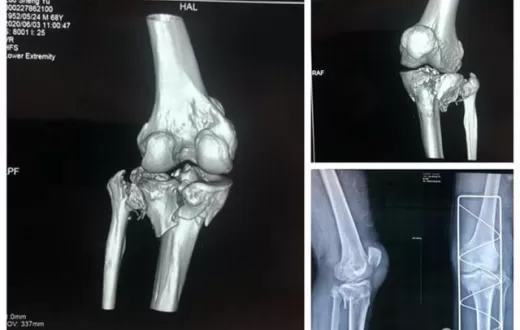

协和江南医院利用3D打印技术,成功为胫骨骨折患者实施手术